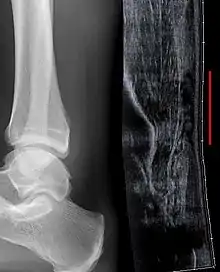

Achilles tendon rupture seen on ultrasound. Note discontinuity over several centimeters (red line). No fracture or avulsion (radiograph).

Ultrasonography can be used to determine the tendon thickness, character, and presence of a tear. It works by sending harmless high frequencies of sound waves through the body. Some of these sound waves reflect back off the spaces between fluid and soft tissue or bone. These reflected images are analyzed and created into an image. These images capture in real time and are helpful in detecting movement of the tendon and visualizing injuries or tears. This device makes it possible to identify injuries and observe healing over time. Ultrasound is inexpensive and involves no harmful radiation. It is operator-dependent and so requires a level of skill and practice for it to be used effectively.[15]

Radiography can also be used to indirectly identify Achilles tendon tears. Radiography uses X-rays to analyze the point of injury. This is not very effective at identifying soft tissue injuries. X-rays are created when high energy electrons hit a metal source. X-ray images are acquired by utilizing the different densities of the bone or tissue. When these rays pass through tissue they are captured on film. X-rays are generally best for dense objects such as bone while soft tissue is shown poorly. Radiography is not the best for assessing an Achilles tendon injury. It is more useful for ruling out other injuries such as heal bone fractures.[14]